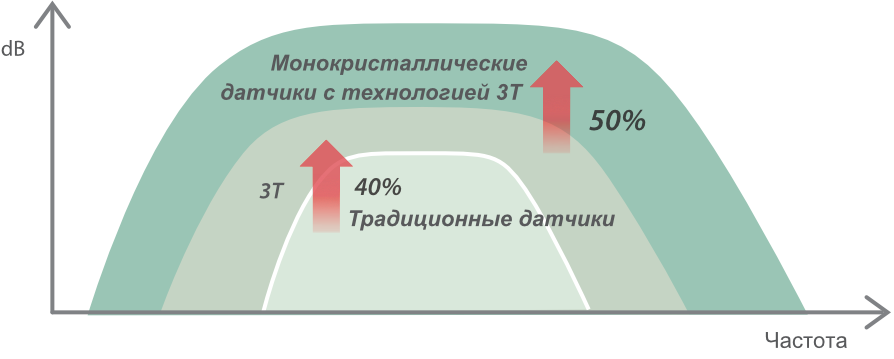

–£―΄―¹–Ψ–Κ–Ψ–Κ–Α―΅–Β―¹―²–≤–Β–Ϋ–Ϋ–Α―è ―²–Β―Ö–Ϋ–Ψ–Μ–Ψ–≥–Η―è –Η–Ζ–≥–Ψ―²–Ψ–≤–Μ–Β–Ϋ–Η―è –¥–Α―²―΅–Η–Κ–Ψ–≤

–£–Ϋ–Β–¥―Ä–Β–Ϋ–Η–Β –≤ DC-80 EXP –¥–Α―²―΅–Η–Κ–Ψ–≤ ―¹–≤–Β―Ä―Ö–≤―΄―¹–Ψ–Κ–Ψ–Ι –Ω―Ä–Ψ–Η–Ζ–≤–Ψ–¥–Η―²–Β–Μ―¨–Ϋ–Ψ―¹―²–Η –Ψ–±–Β―¹–Ω–Β―΅–Η–≤–Α–Β―² –¥–Μ―è –£–Α―¹ –Ω―Ä–Β–≤–Ψ―¹―Ö–Ψ–¥–Ϋ–Ψ–Β –Κ–Α―΅–Β―¹―²–≤–Ψ –≤–Η–Ζ―É–Α–Μ–Η–Ζ–Α―Ü–Η–Η.

–€–Ψ–Ϋ–Ψ–Κ―Ä–Η―¹―²–Α–Μ–Μ–Η―΅–Β―¹–Κ–Η–Β –¥–Α―²―΅–Η–Κ–Η ―¹ ―²–Β―Ö–Ϋ–Ψ–Μ–Ψ–≥–Η–Β–Ι 3–Δ?

–ë–Μ–Α–≥–Ψ–¥–Α―Ä―è ―¹–Ψ―΅–Β―²–Α–Ϋ–Η―é ―²–Β―Ö–Ϋ–Ψ–Μ–Ψ–≥–Η–Η 3–Δ? (–Δ―Ä–Ψ–Ι–Ϋ–Ψ–Ι ―¹–Ψ–≥–Μ–Α―¹―É―é―â–Η–Ι ―¹–Μ–Ψ–Ι, ―²–Β―Ö–Ϋ–Ψ–Μ–Ψ–≥–Η―è –Ω–Ψ–Μ–Ϋ–Ψ―¹―²―¨―é ―Ä–Α–Ζ–¥–Β–Μ–Β–Ϋ–Ϋ―΄―Ö –Κ―Ä–Η―¹―²–Α–Μ–Μ–Ψ–≤, ―²–Β―Ä–Φ–Ψ–Κ–Ψ–Ϋ―²―Ä–Ψ–Μ―¨ –Α–Κ―É―¹―²–Η―΅–Β―¹–Κ–Ψ–Ι –Μ–Η–Ϋ–Ζ―΄) –Η –Φ–Ψ–Ϋ–Ψ–Κ―Ä–Η―¹―²–Α–Μ–Μ–Η―΅–Β―¹–Κ–Η―Ö –¥–Α―²―΅–Η–Κ–Ψ–≤ –Ψ–±–Β―¹–Ω–Β―΅–Η–≤–Α–Β―²―¹―è –Κ–Α–Κ –±–Ψ–Μ–Β–Β –≤―΄―¹–Ψ–Κ–Α―è ―Ä–Α–Ζ―Ä–Β―à–Α―é―â–Α―è, ―²–Α–Κ –Η –Ω―Ä–Ψ–Ϋ–Η–Κ–Α―é―â–Α―è ―¹–Ω–Ψ―¹–Ψ–±–Ϋ–Ψ―¹―²―¨, –≤ ―Ä–Β–Ζ―É–Μ―¨―²–Α―²–Β ―΅–Β–≥–Ψ ―Ä–Β―à–Α–Β―²―¹―è –Ω―Ä–Ψ–±–Μ–Β–Φ–Α –Η―¹―¹–Μ–Β–¥–Ψ–≤–Α–Ϋ–Η–Ι ―²–Β―Ö–Ϋ–Η―΅–Β―¹–Κ–Η ―¹–Μ–Ψ–Ε–Ϋ―΄―Ö –Ω–Α―Ü–Η–Β–Ϋ―²–Ψ–≤.